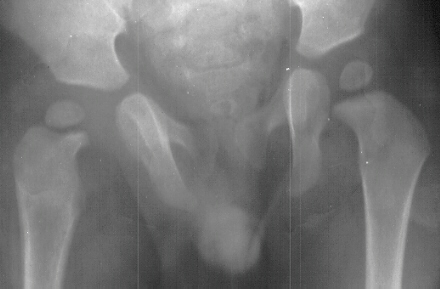

- 2 month Office Follow Up: Rt hip Xray: progressive destruction of capital

femoral epiphysis, cystic changes in metaphysis consistent with AVN.

- Age 6: Valgus osteotomy for subluxation and 2cm leg length inequality.

- Age 15: Valgus osteotomy for hip incongruity.

- Age 20: Hip arthroscopy. Hip fusion recommended.

This case is an example of untreated septic arthritis which caused avascular

necrosis of the proximal femur. The primary cause of this is undrained

septic hip. Repeated aspiration is not adequect treatment of a septic hip.